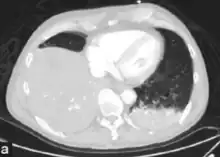

Pneumococcal antigen (cell wall C polysaccharide) may be detected in various body fluids. Older detection kits, based on latex agglutination, added little value above Gram staining and were occasionally false-positive. Better results are achieved with rapid immunochromatography, which has a sensitivity (identifies the cause) of 70–80% and >90% specificity (when positive identifies the actual cause) in pneumococcal infections. The test was initially validated on urine samples but has been applied successfully to other body fluids.[28] Chest X-rays can also be conducted to confirm inflammation though are not specific to the causative agent.[29][13]

Chest X-ray pneumonia

CT pneumonia